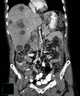

An ameboma, also known as an amebic granuloma, is a rare complication of Entamoeba histolytica infection, where in response to the infecting amoeba there is formation of annular colonic granulation, which results in a large local lesion of the bowel. Presentation The ameboma may manifest as a right lower quadrant abdominal mass, which may be mistaken for carcinoma, tuberculosis, Crohn's disease, actinomycosis, or lymphoma. [Source: Wikipedia ]